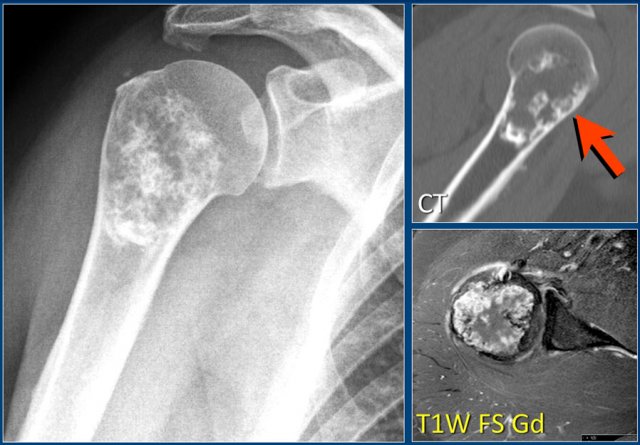

Chondroblastoma (4)

Here a lesion located in the epi- and metaphysis of the proximal humerus.

The lesion is predominantly calcified.

Coronal T1W image shows lobulated margins and peripheral low SI due to the calcifications.

Notice the surrounding decreased signal intensity of the bone marrow, consistent with edema.

Edema almost always accompanies chondroblastoma, but is unusual in other chondroid tumors, like enchondroma or low-grade chondrosarcoma.

Diagnosis: Chondroblastoma.